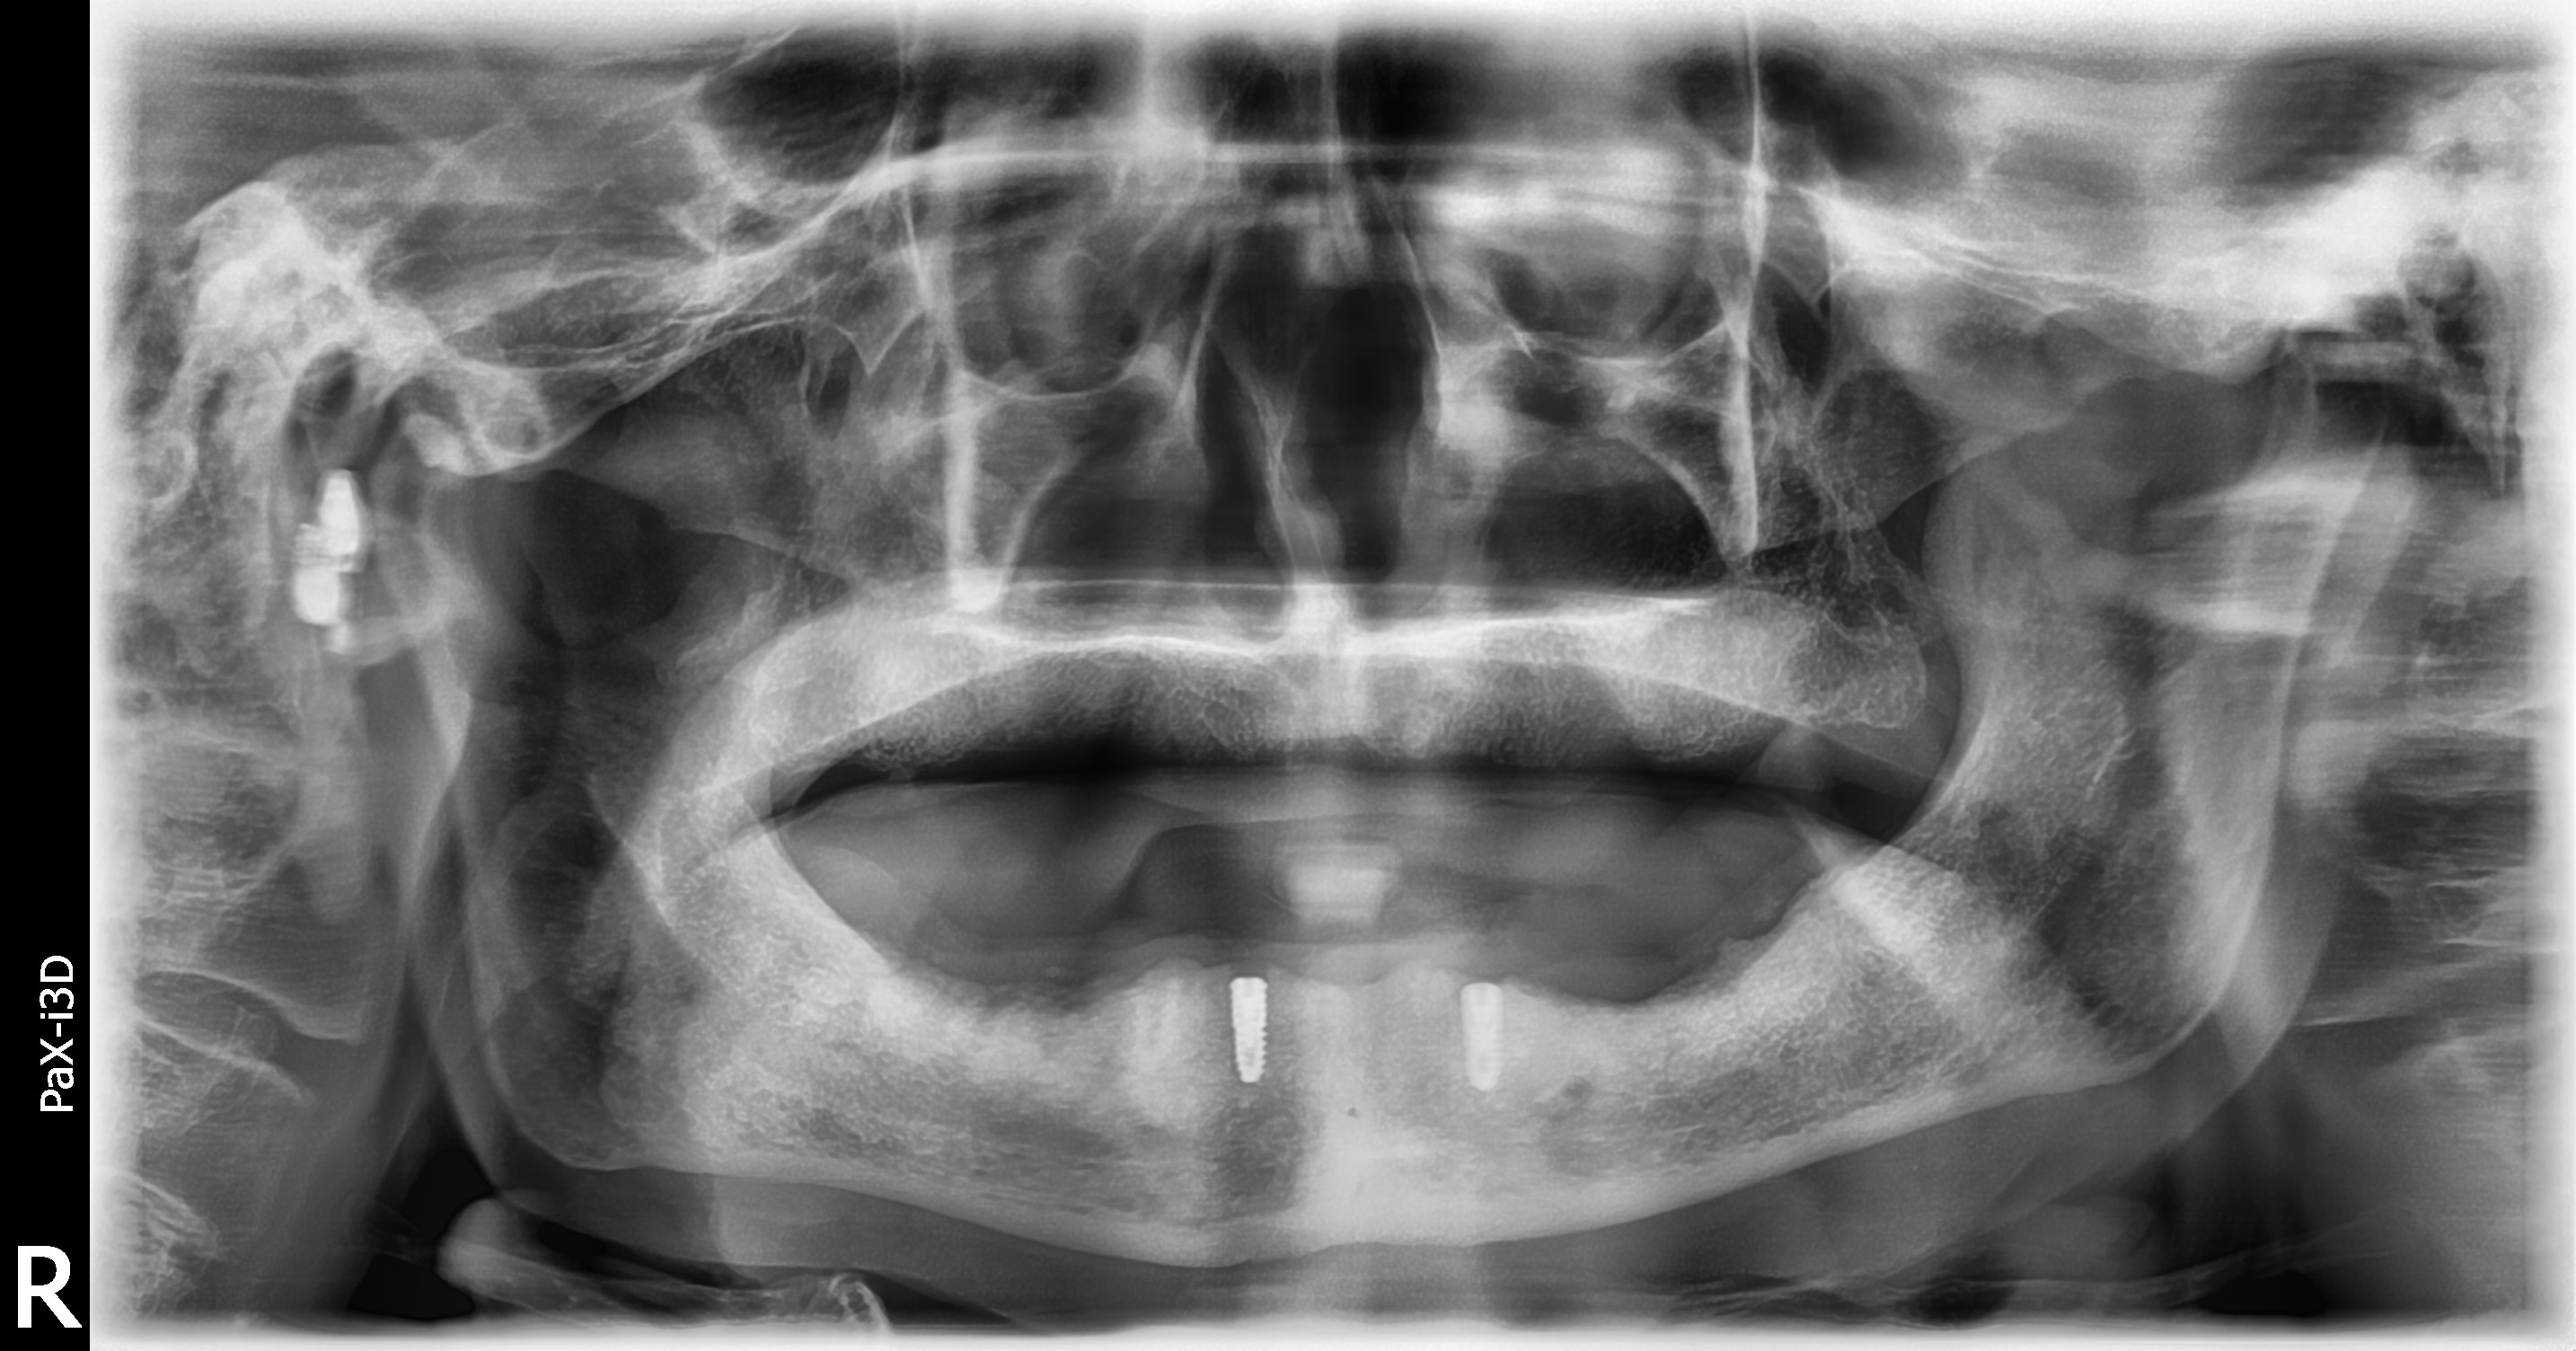

임플란트 틀니

상악동 거상술